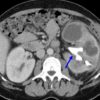

Viêm thận bể thận

» Thông tin: Nữ giới – 51 tuổi.

» Lâm sàng: Đau thắt lưng + Sốt.